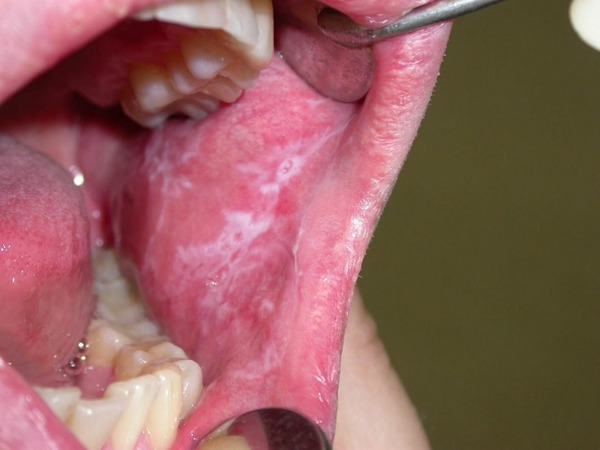

Поражения слизистой. Об одном из них мы уже сказали. Это ксеростомия — сухость во рту. Из-за температурного и токсичного воздействия горячего дыма на чувствительный эпителий возникают очаги ороговения с белым налётом вокруг них (лейкоплакия, или никотиновый стоматит). Хрупкая слизистая просто не выдерживает высокой температуры и систематической интоксикации, поэтому в дело вступает защитная реакция — эпителий сначала становится очень тонким, начинает часто кровоточить, а затем просто огрубевает.

Лейкоплакия — это то, что в гистологии называется метаплазией. Ещё не онкология, но уже неприятный звоночек. В норме каждый тип эпителия имеет свои особенности, в зависимости от того, где он живёт. У эпителия дыхательного тракта есть реснички, чтобы выталкивать пыль и грязь наружу. У эпителия кожи есть прочный защитный слой из кератина, чтобы создавать труднопроницаемый барьер между агрессивной внешней средой и нежными тканями внутри.

Эпителий слизистой оболочки полости рта в норме имеет морфологический тип «многослойного плоского» и никогда не ороговевает. У здоровых людей белая линия метаплазии и трансформации в ороговевающий тип встречается только по линии смыкания зубов, где щека часто прикусывается. Ороговение — это форма защиты ткани от хронического повреждения. К сожалению, метапластические процессы можно рассматривать как предраковые. Так что, в случае курильщиков — это уже очень важный звоночек.

Лейкоплакия курильщика (никотиновый стоматит) собственной персоной. Белые области — огрубевший эпителий слизистой.